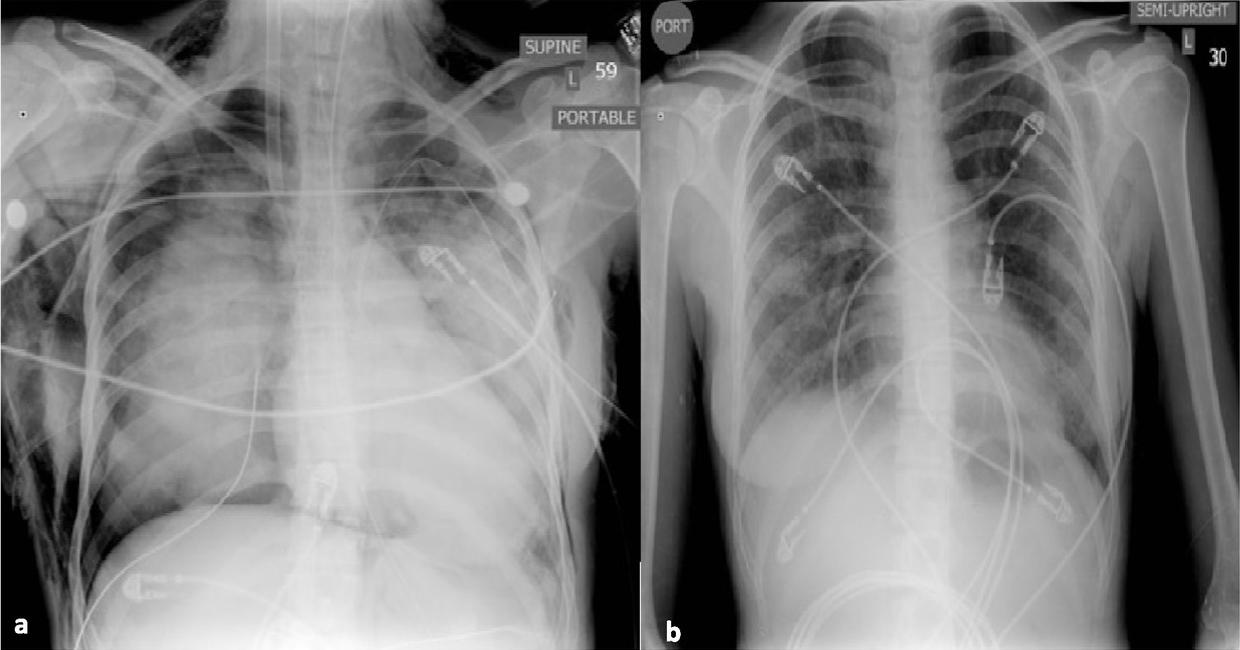

Fig. 2